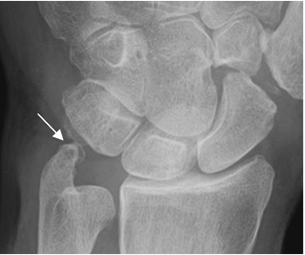

Fig 87. Impactación ulnar.

Rx AP. Prominencia de la apófisis estiloides de la ulna, que ocasiona lesión osteocondral del piramidal.